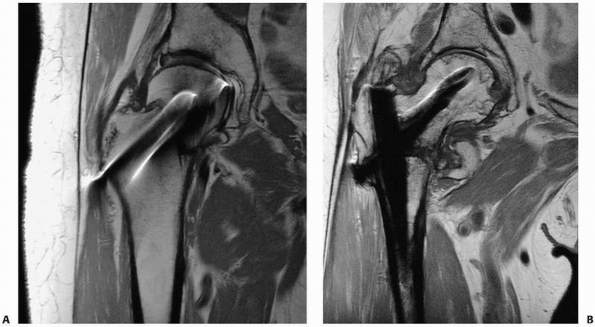

![]() |

|

FIGURE 16-6 A, B.

Anteroposterior and lateral radiographs of a patient who had external fixation of a distal tibia fracture with progressive deformity. C, D. Computed tomography of the nonunion with two-dimensional reconstructions in the coronal and sagittal planes provides unambiguous evidence of fracture nonunion. |